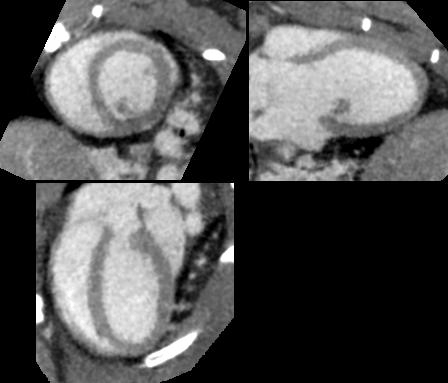

大鼠心脏CT动态成像

优势:小动物CT设备在小动物骨和肺部组织检查等方面具有独特的优势。对于骨的研究(离体实验),如果在小梁水平上分析,一般要求空间分辨率较高,通常在15μm以内;活体小动物的肺部组织检查时(活体实验),空间分辨率在50~200μm即可,呼吸门控技术的加入也有助于图像伪影的消除。

不足:血管、内脏等软组织成像需要借助造影剂增强对比观察。

应用:小动物CT的应用领域主要有骨研究(如骨小梁)、肺部组织、生物材料(如仿生材料生物支架的孔隙率、强度等)、疾病机制研究(如疾病状态对骨骼发育、修复的影响)、新药开发(如骨质疏松症及疗效评价)等,主要是对活体小动物的硬组织和相关软组织的扫描成像分析,集中于骨领域研究。目前还有一些新型的造影剂也逐步应用于小动物CT的研究。相对于临床上的传统碘剂造影剂,这些新型造影剂的特点是时程长、与周围组织的对比明显,通常用于活体小动物的血管造影和连续观察。